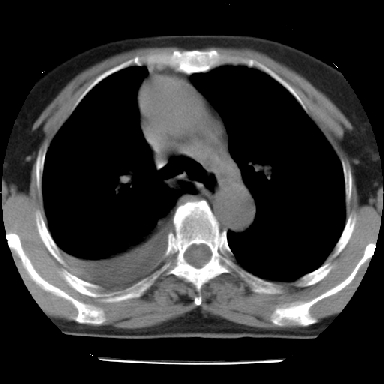

以下是引用苯小孩在2007-4-13 16:20:00的发言:[br]1、右下肺中央型肺癌并阻塞性肺不张、肺内转移、胸椎右侧附件亦有转移<横断层面第8层>.[br]2、右侧胸腔积液.

以下是引用swyyy2007在2007-4-13 15:31:00的发言:[br]右肺门下区肿块,右肺下叶支气管阻塞,右肺下叶不张,右侧大量胸腔积液,右肺中叶见结节状高密度影,边缘清,纵隔内见肿大淋巴结。首先考虑右下肺中心型肺癌伴右肺下叶不张、中叶、纵隔淋巴结转移。右侧胸腔积液。